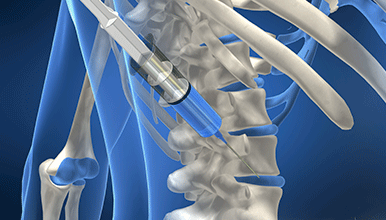

신경차단술 | 수술없이 통증을 치료합니다.

이동식 X-ray 기계(C-arm)를 이용해 병변 부위를 실시간으로 확인할 수 있어 높은 정확도로 치료할 수 있는 방법입니다. 신경 주변 가까이 접근해 약물을 주입, 염증과 부종을 해소하고 통증을 완화시킵니다.